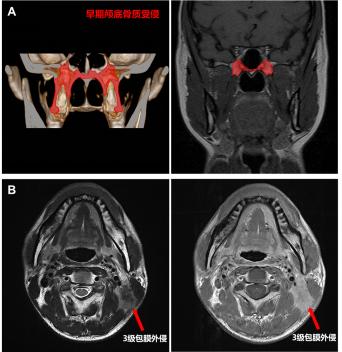

随着核磁共振技术的发展,鼻咽癌早期颅底骨质受侵(仅翼突或蝶骨基底受侵)患者的检出率显著提高,占到所有患者的10-20%,原发灶分期为T3患者的20-30%。既往研究报道早期颅底骨质受侵患者预后较好,或可豁免高强度的化疗。本次研究结果显示,早期颅底骨质受侵的T3患者的5年生存率为91.9%,显著优于其余T3患者(88.8%),且与T2患者相似(91.5%)。因此,建议将轻度颅底骨质受侵降为T2。

颈部严重淋巴结包膜外侵(即3级包膜外侵,肿瘤突破淋巴结包膜侵犯淋巴结周围邻近结构)患者往往临床预后较差,治疗后极易发生复发转移。研究发现原淋巴结分期为N1和N2患者中严重颈部淋巴结包膜外侵患者5年生存率分别为82.0%和77.1%,与N3的78.7%接近。因此,建议严重颈部淋巴结包膜外侵升级为N3。

新版鼻咽癌解剖结构调整示意图

A早期颅底骨质受侵:仅有翼突或蝶骨基底的颅底骨质受侵

B 3级淋巴结包膜外侵:肿瘤突破淋巴结包膜侵犯淋巴结周围邻近结构